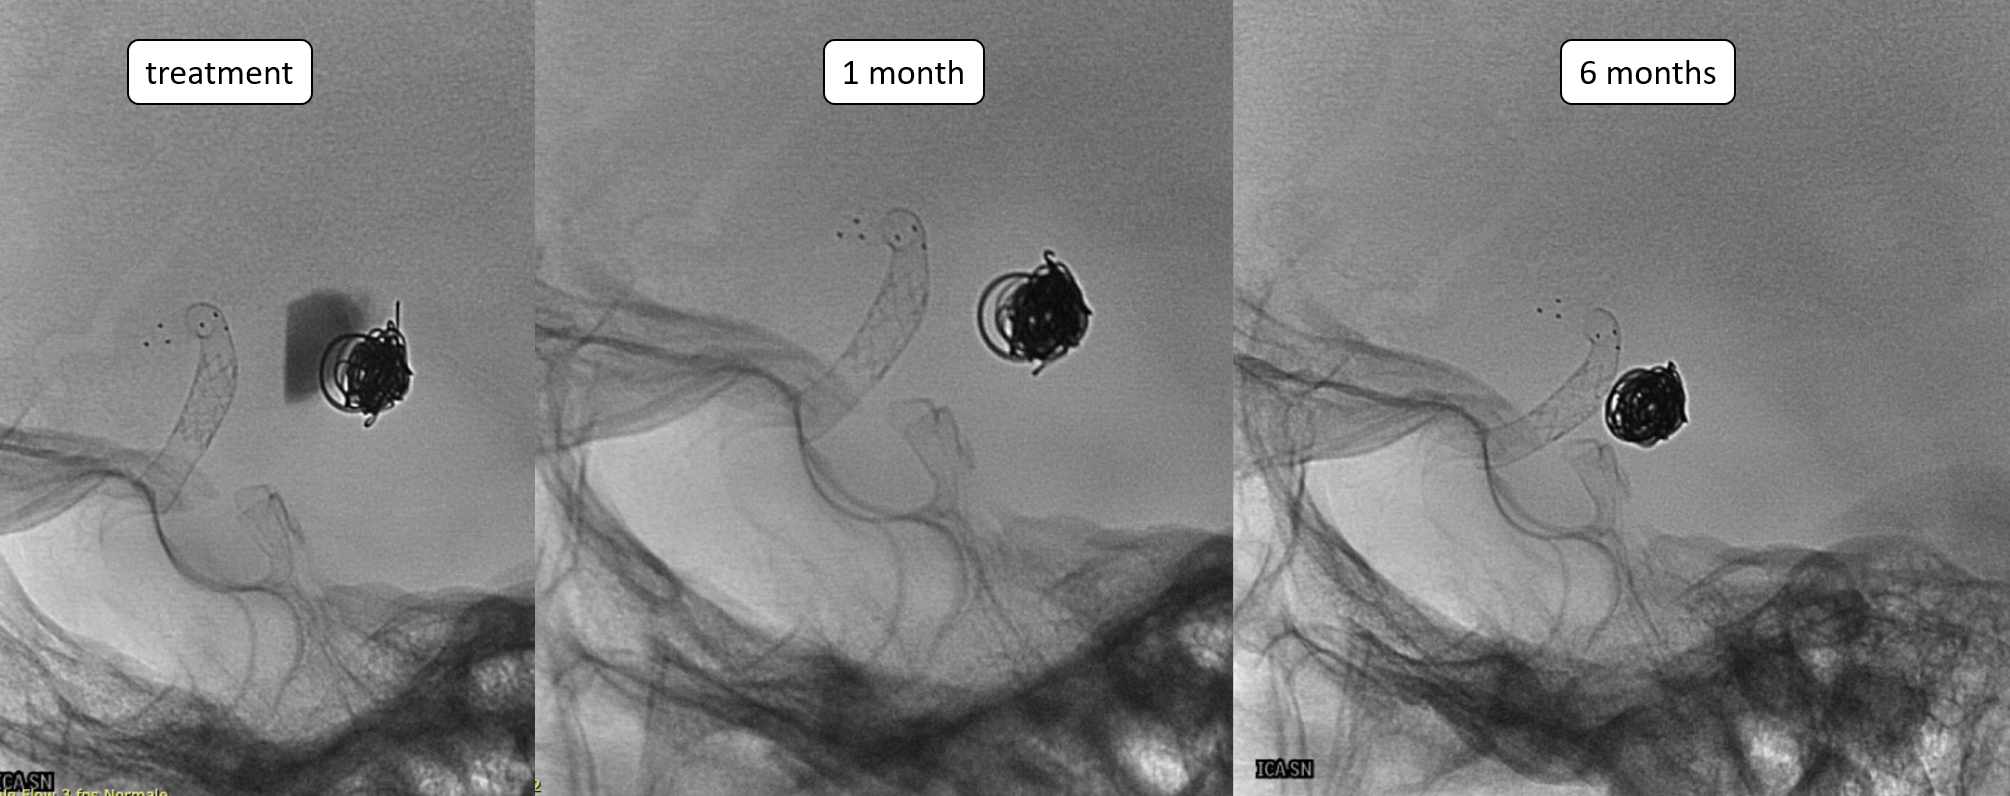

Beautiful simple images of aneurysm shrinkage and mass effect relief

Important Case of Aggressive Anterior Choroidal Aneurysm

This is a specific subtype of ever-growing choroidal aneurysm that is extremely difficult to solve without complete occlusion of the aneurysm and the choroidal artery. Fortunately, perhaps because of the unique aneurysm biology, choroidal occlusion tends to be mildly or not at all symptomatic.

A young man with an unruptured but symptomatic dissecting aneurysm at the origin of the Anterior Choroidal artery. Treated in acute phase with coils; in the meantime the aneurysm has grown.

One month later the aneurysm was still growing — as they frequently do.

A Bentley Coronary Stent 3 x 8 mm was implanted, progressively inflated (even with a 3.5 PTA balloon) until no more contrast entered the aneurysm. The USA version of Bentley is the Papyrus — Bentley is better.